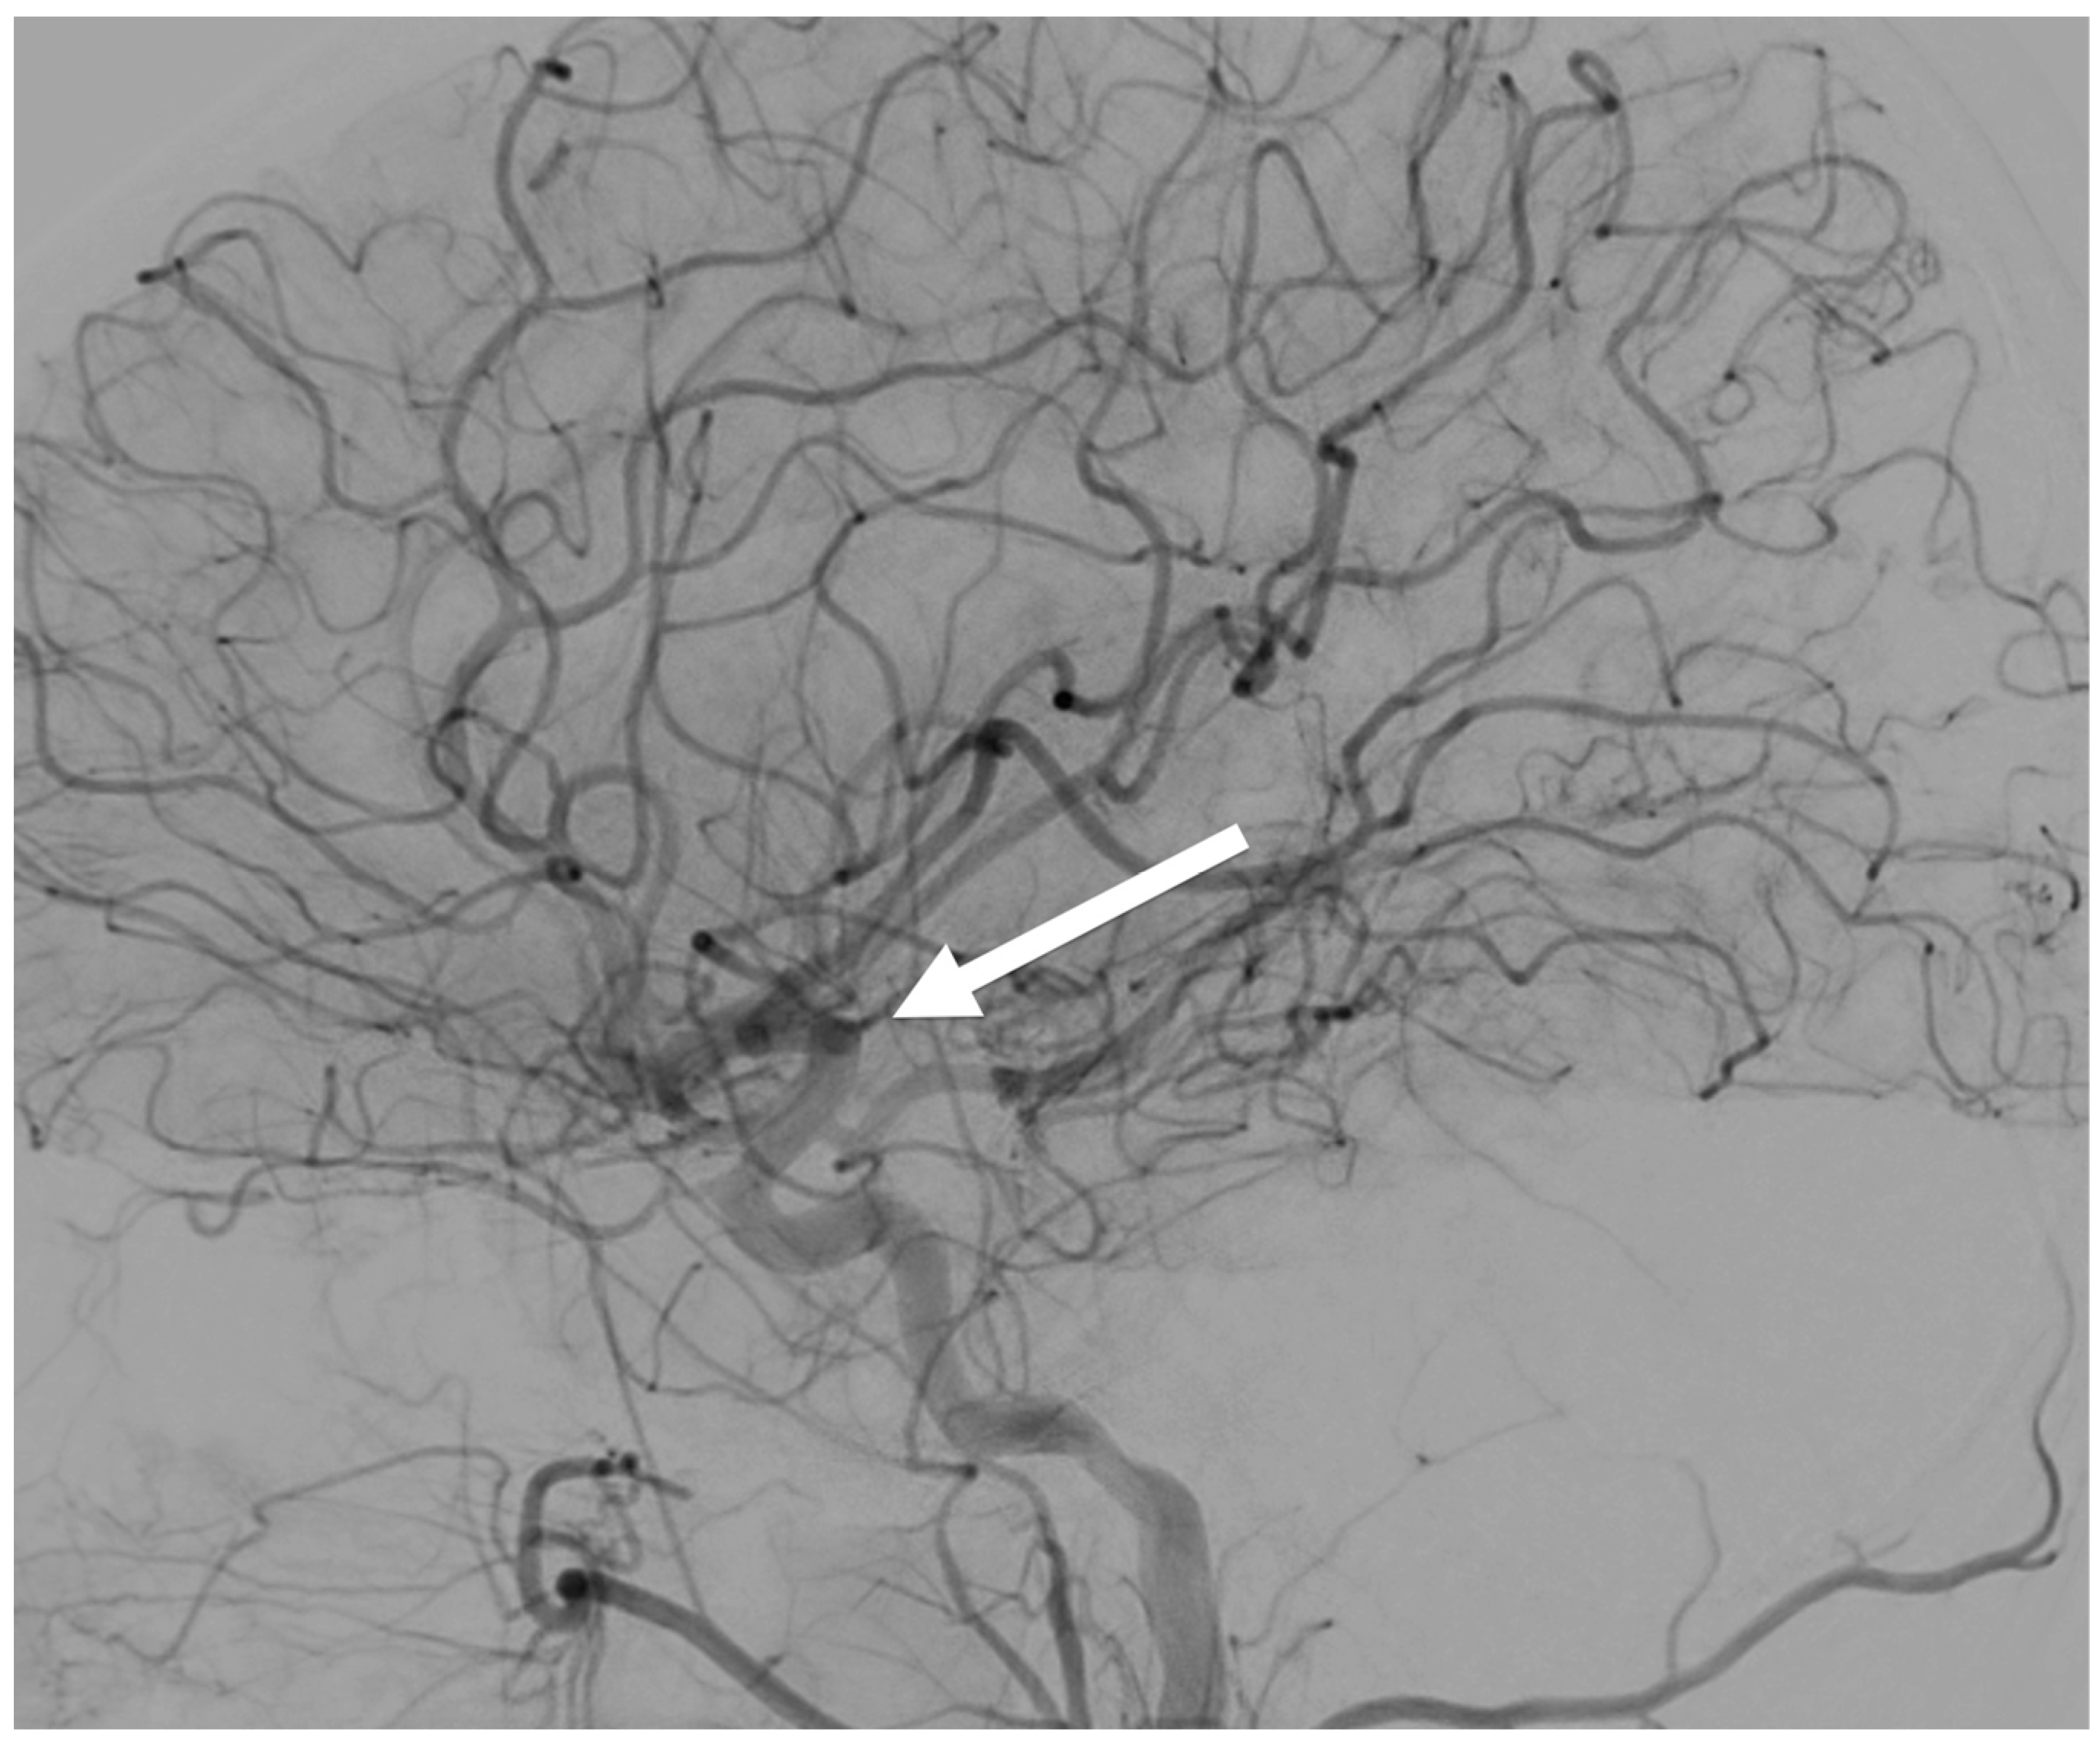

| 3D dynamic imaging stereovideography (Figure 5, Figure 6 and Figure 9) | 20–200 μm Static or moving image intensifiers with high-speed cameras | 1 s, as required by IR/10–10000 | 0.02–1.1 mSv min−1/0.08–0.9 mSv min−1/0.02–0.08 mSv min−1 | 50–1100 /10–500/variable VD and VH/0.02–0.2 |